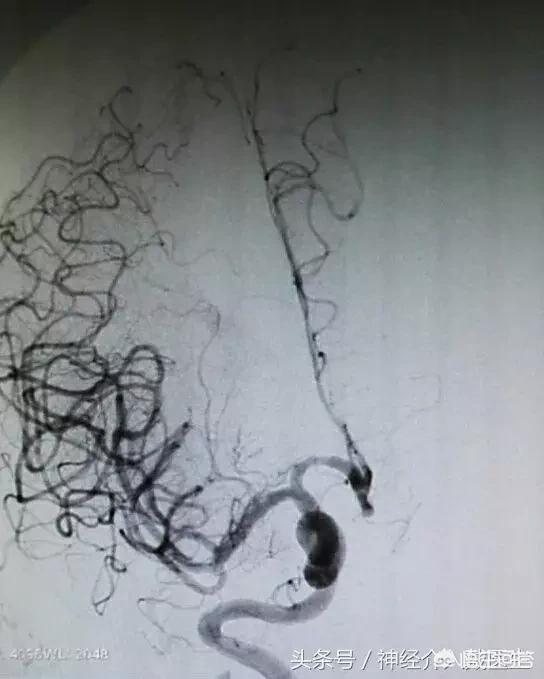

支架机械取栓治疗是目前治疗急性脑梗死的最为先进的技术手段,和溶栓治疗相比具有安全性高、作用显著和时间窗长等优点,目前已在国内外大型医疗中心普及。支架机械取栓是将一条直径0.3毫米左右的导丝从患者股动脉穿入体内,在透视监示下通过脑内大血管中的血栓进行定位,再用微导管将镍钛合金的取栓支架输送到血栓部位,释放支架后,镍钛合金支架自动膨胀展开,形成圆柱形网状结构,与血管壁贴合、嵌入血栓。术者将取栓装置抽离,栓子同时被拽出体外。

机械取栓具有血管再通率高、脑出血发生率低、再通时间、治疗时间窗延长等优点。目前很多学者认为,只要MRI显示存在较大的缺血半暗带,就应该积极开通血管,但治疗时间窗有待进一步研究。机械取栓也存在因手术准备及操作延迟血管再通、对操作人员及设备要求较高等缺点。